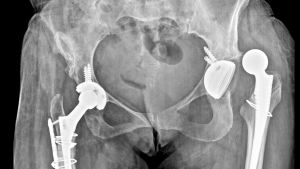

Beidseitige Hüftprothesen – ein drastisches Ergebnis eines vermeidbaren Risikos.

Ein Implantat ersetzt Stabilität – Prävention wäre besser gewesen.

Nebenbei bemerkt: Die Lebensqualität von Menschen, die einmal an der Hüfte operiert wurden, ist oft massiv eingeschränkt. Da will wirklich niemand freiwillig hin.